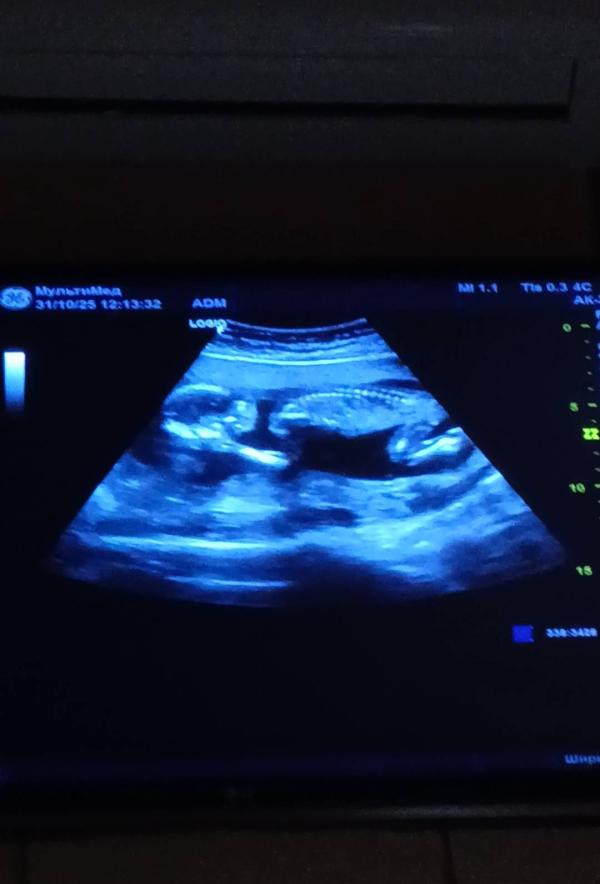

Сходила на УЗИ.

Всё хорошо.

Малыш опережает, поставили 17 недель ровно (пдр 10.04, было 16.04)

Весит уже 180грамм)

Шейка 37 как и была !

Я попросила написать пол в конвертик, но в конце врач сказала что она не уверенна и писать не будет, она видит только на 80%

Качество фото не очень...скрин с видео!))